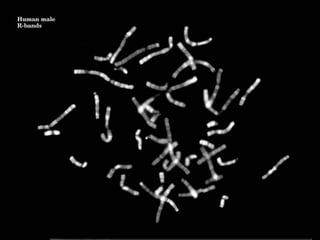

Human male

G-banda

G banding

• Most common method used

• Chromosomes treated with trypsin

– denatures protein

• Giemsa stain

–

each chromosome characteristic light and dark bands

400 bands per haploid genome

Each band corresponds to 5-10 megabases

High resolution (800 bands ; prometaphase chromosome)

– use methotrexate and colchicine

• Dark bands are gene poor

•

Metaphase spreads

Count chromosomes in 10-15 metaphases

If mosaicism suspected, count 30

Detailed analysis of 3-5 metaphases

Used to photograph and cut out

Now computer programmes